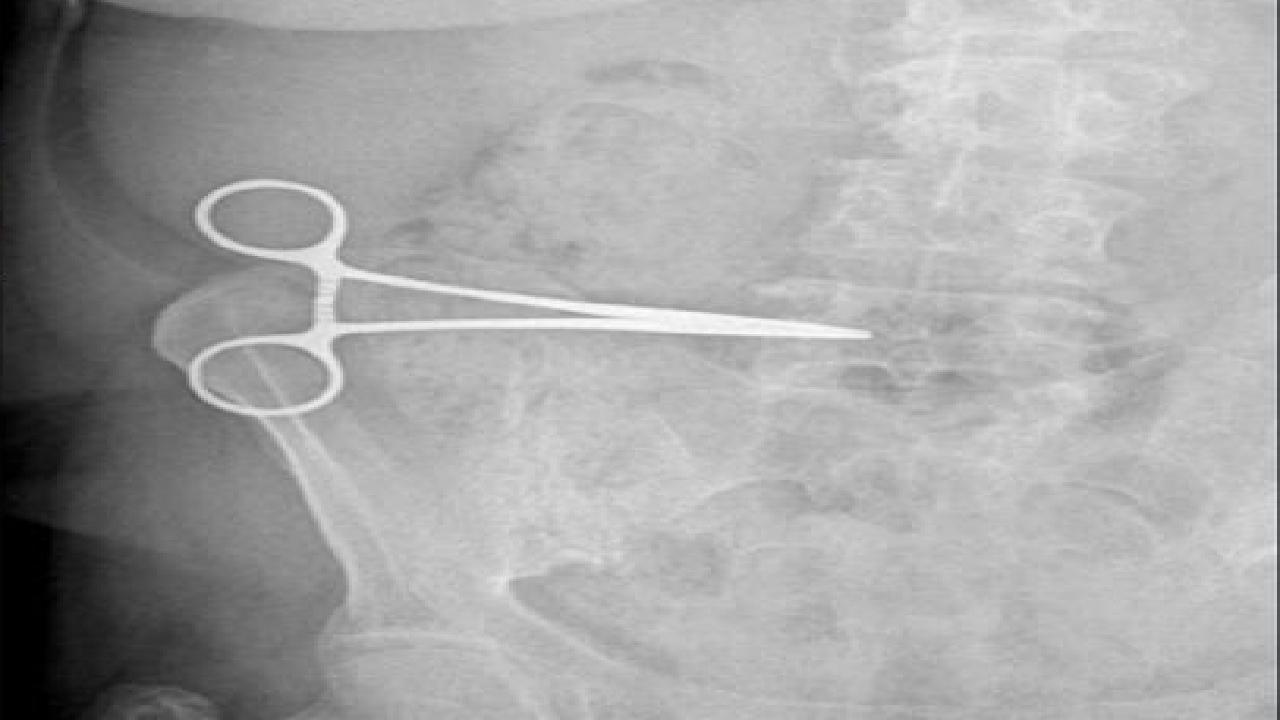

Yaklaşık 2 ay bu sorunu yaşayan kadın, Söke Devlet Hastanesine giderek çektirdiği röntgenle karnında makas olduğunu öğrendi.

Röntgeni Aydın'daki özel hastaneye götüren kadının karnındaki makas, operasyonla çıkarıldı.